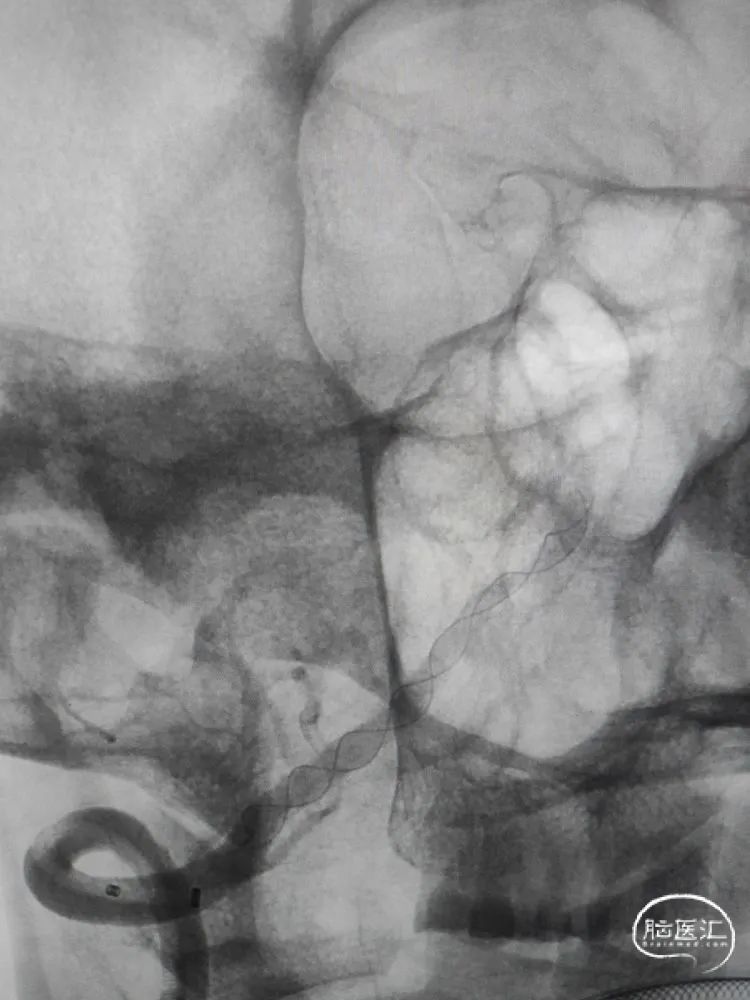

术前影像学检查:全脑血管造影检查提示右侧椎动脉V5段(颅内段)夹层动脉瘤。

动脉瘤大小约5.45mm×7.31mm,动脉瘤远端椎动脉汇合前管径约2.77mm,动脉瘤近端V4段管径约3.80mm,V5段全长约35mm,对侧椎动脉正常。

正位造影